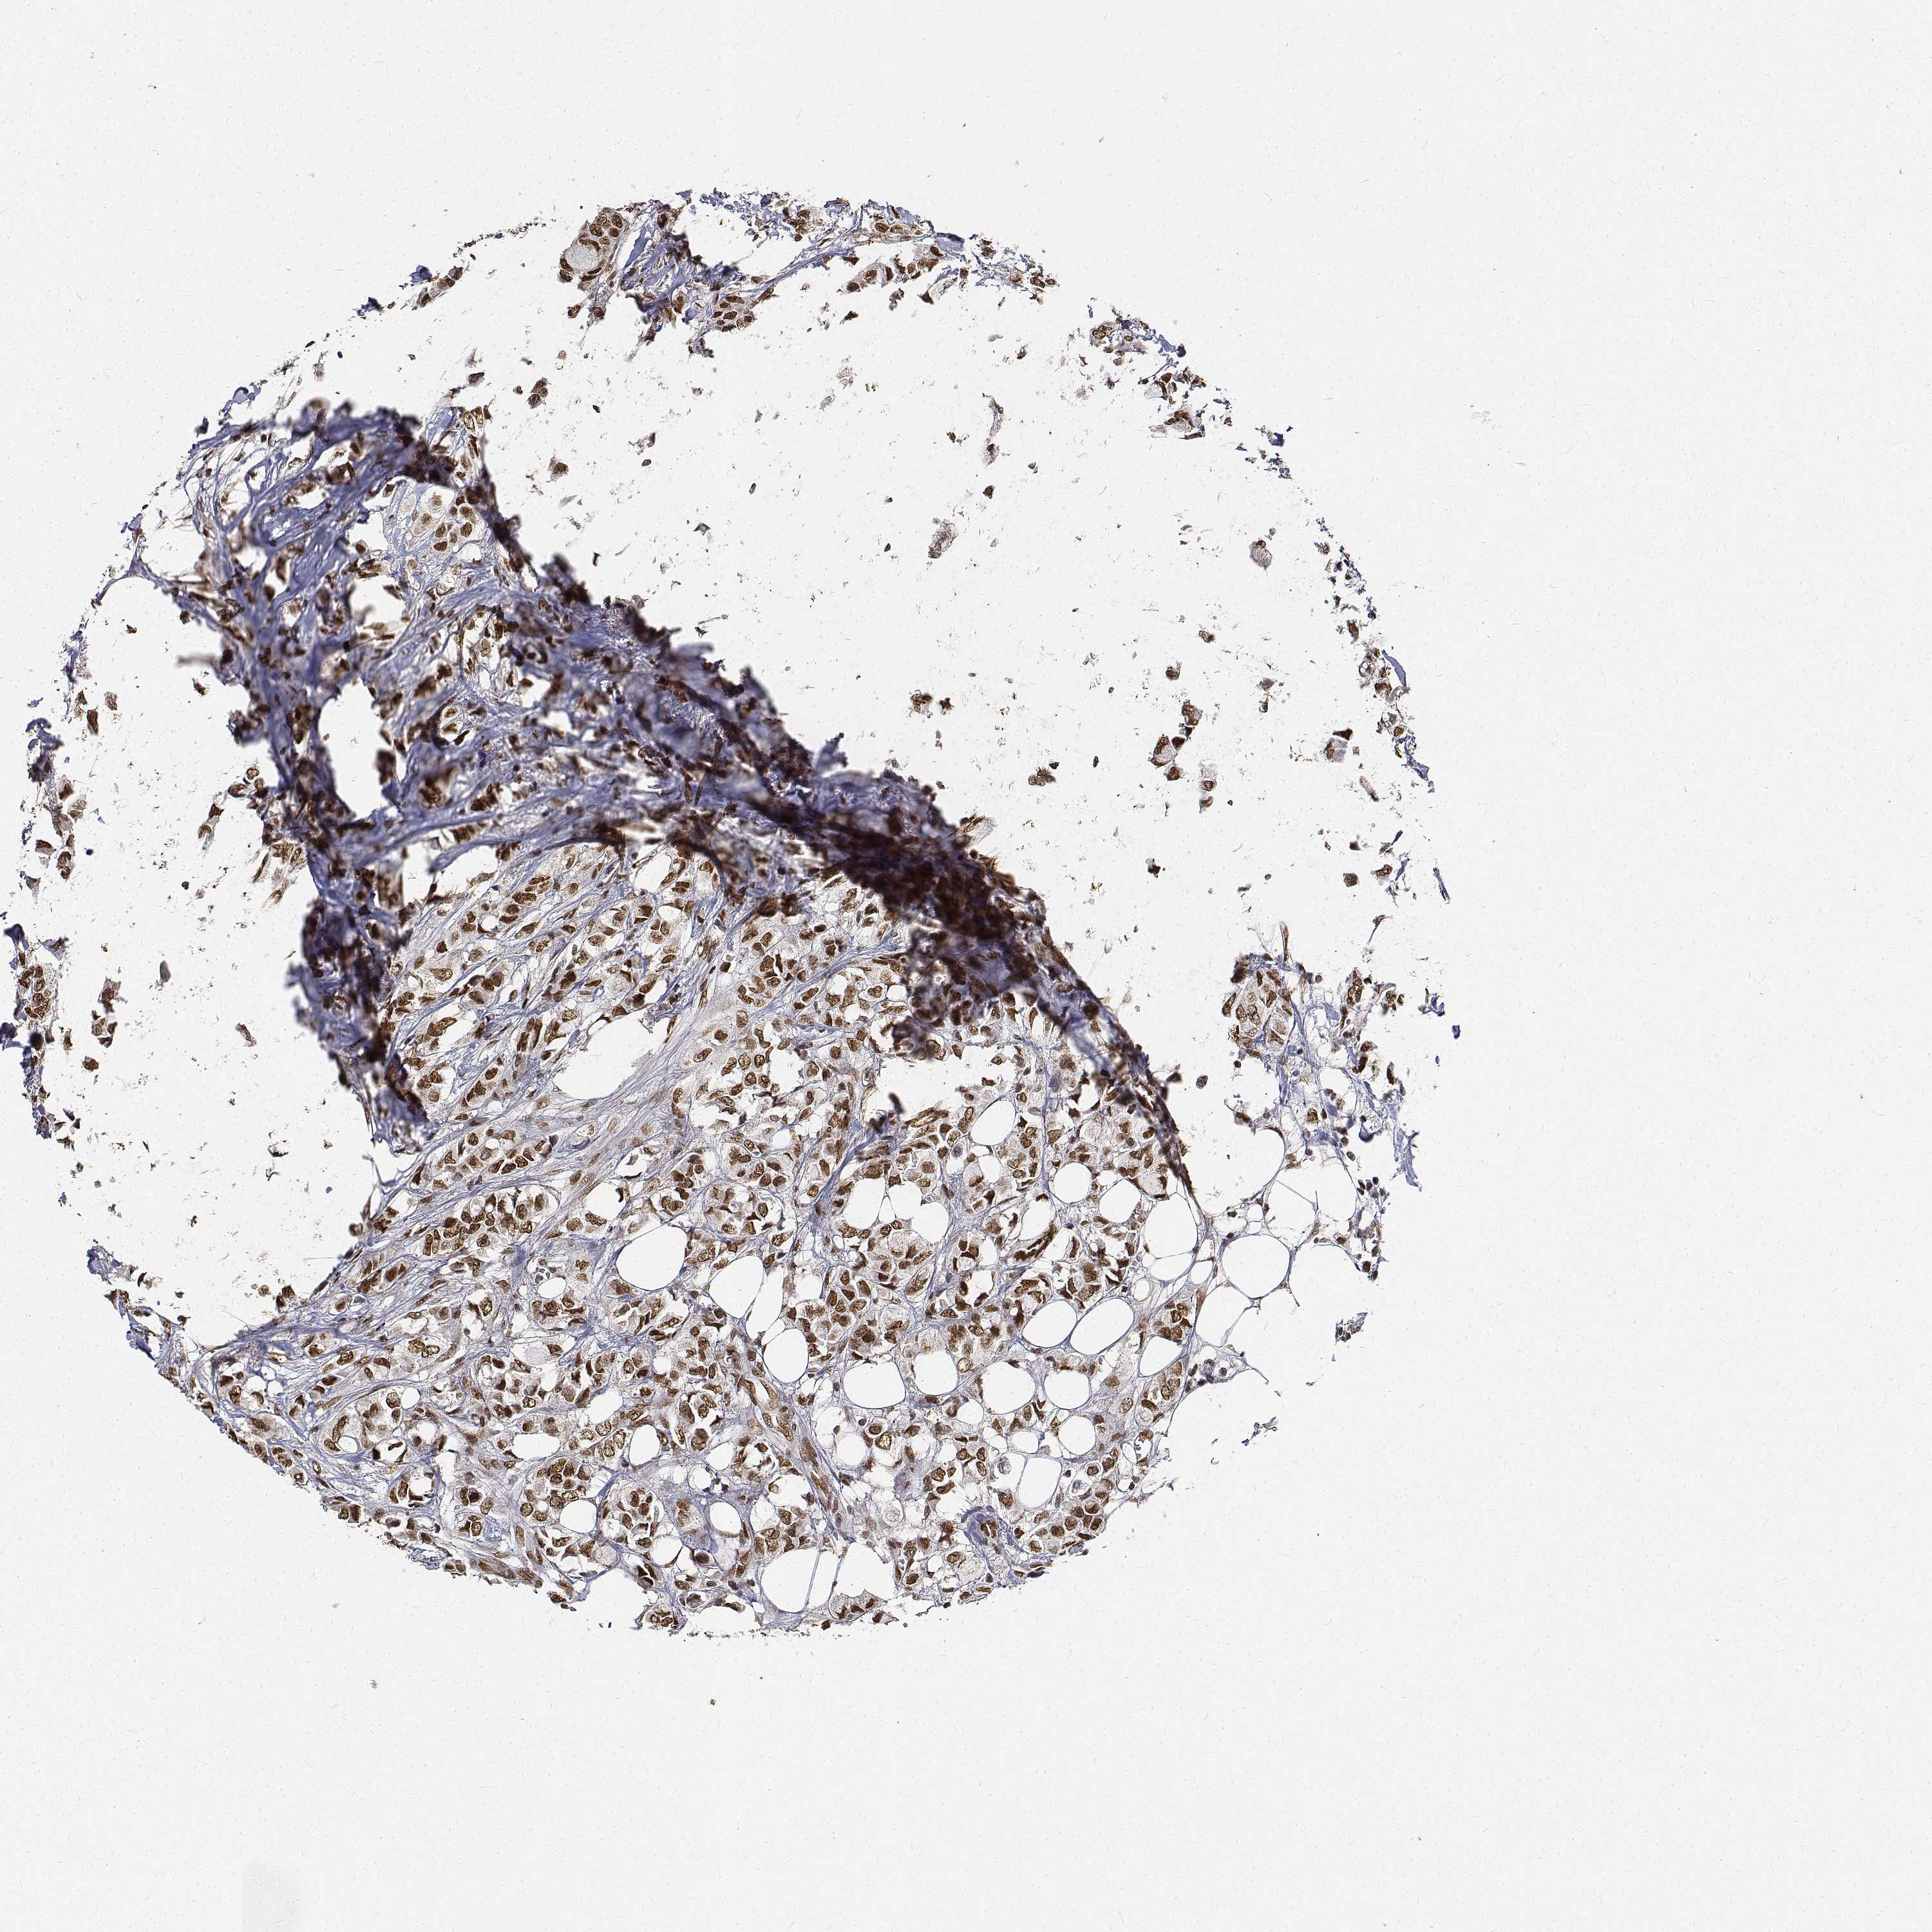

CANCER BREAST CANCER Show tissue menu

BRCA TCGA BRCA VALIDATION PROTEIN EXPRESSION

ANTIBODIES

AND

VALIDATION